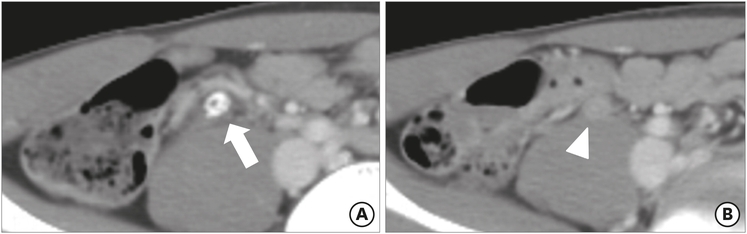

The mean maximal diameter of the appendix was 9.56 mm in the true appendicitis group and 7.28 mm in the negative appendicitis group. According to the definition of appendiceal enlargement (>8 mm in maximal diameter), 3 patients (23.1%) in the negative appendicitis group had an enlarged appendix, while 60 patients (68.2%) in the true appendicitis group had appendiceal enlargement (Fig. 1). This difference was statistically significant (p=0.002). Periappendiceal fat inflammation, or fat stranding, was noted in 2 patients (15.4%) in the negative appendicitis group and 43 patients (48.9%) in the true appendicitis group (p=0.023) (Fig. 2). For the other measured findings, there were no significant differences between the groups. The ACT findings are summarized in Table 2, along with their odds ratios and 95% confidence intervals (CIs).

Fig. 1

Preoperative abdominal computed tomography findings for a 9-year-old male patient, who was demonstrated to have serositis: (A) appendicolith with focal wall thickening (arrow) and (B) adjacent mesenteric lymphadenopathy (arrowheads) were observed, but there was no associated periappendiceal fat infiltration or appendiceal enlargement.